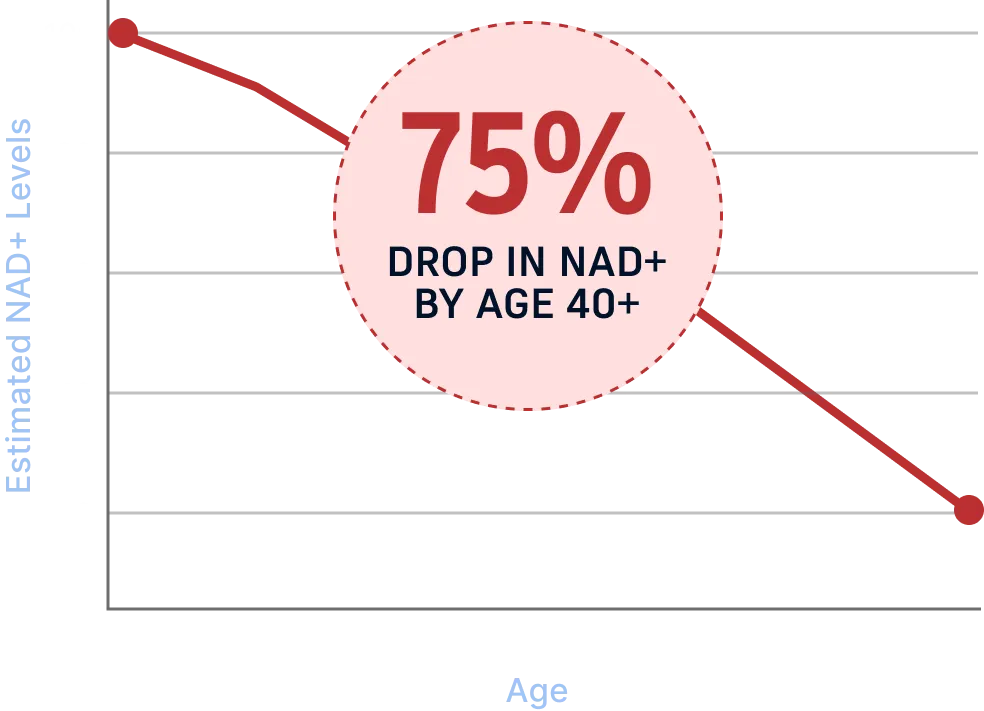

The Real Reason Men Lose Energy After 40

NAD+ naturally declines as men age, slowing

the

cellular processes that keep you energized, focused, and

resilient. Lower NAD+ leads to weaker circulation,

slower recovery, reduced mental clarity, and a drop in

daily performance.

Energy Decline

Reduced Focus

Slower Recovery

Weaker Circulation